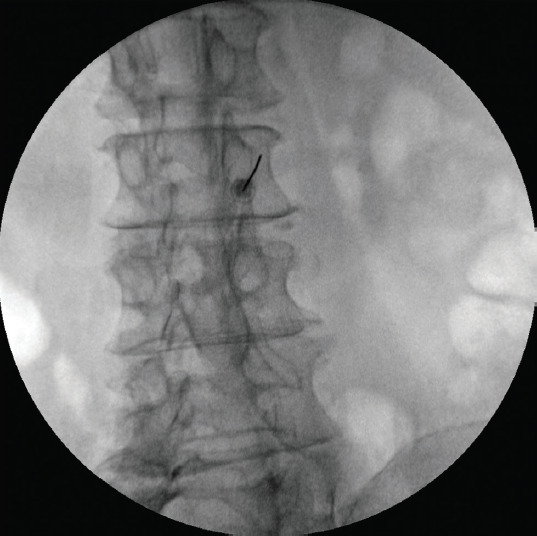

Objectives: To assess how facet medial branch radiofrequency thermocoagulation (FMB-RFT) outcomes are affected by severe facet joint osteoarthritis (FJO).

Methods: This retrospective study involved 91 individuals with lumbar facet joint disease-related chronic lower back pain (CLBP), all of whom underwent FMB-RFT. The patients were assigned to 3 groups using the Weishaupt facet grading system (WFGS). Pain scores were assessed prior to treatment, as well as at the 1-, 6-, and 12-month marks.

Results: Based on the WFGS, 38 of the 91 patients were assigned a grade 1 FJO, 28 a grade 2 FJO, and 25 a grade 3 FJO. The percentage of patients in each group who saw a 50% or greater improvement in their pain scores at 1, 6, and 12 months did not differ significantly.

Conclusion: For patients with CLBP, FMB-RFT has been shown to be safe and effective in both the short and long terms. The results from FMB-RFT do not seem to be affected by the severity of FJO.